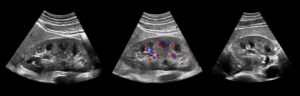

До внедрения оценки сосудистого кровотока (допплерометрии), диагносты не могли дифференцировать новообразования между собой.

Однако на основании ряда признаков, врач, еще на этапе не инвазивной диагностики, может предположить природу злокачественного или доброкачественного процесса (ангиомиолипома, нефробластома и другие).

- при доплерографии в раке выявляется дефект окрашивания, где пропадает нормальная архитектоника почечных сосудов, степень васкуляризации может быть различной – от полного отсутствия изображения сосудов до высокой васкуляризации с множественным усилением цветового сигнала.